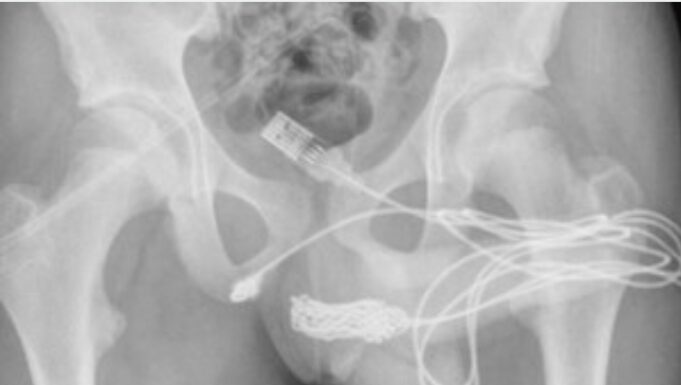

Las radiografías posteriores revelaron que había un verdadero enredo de cable dentro del adolescente. Por ello, los cirujanos hicieron una incisión en la región entre sus genitales y el ano para sacarlo. Primero tiraron del extremo enrollado a través del agujero, cortándolo libre del resto del cable antes de quitar los trozos restantes, literalmente tirando del enchufe.